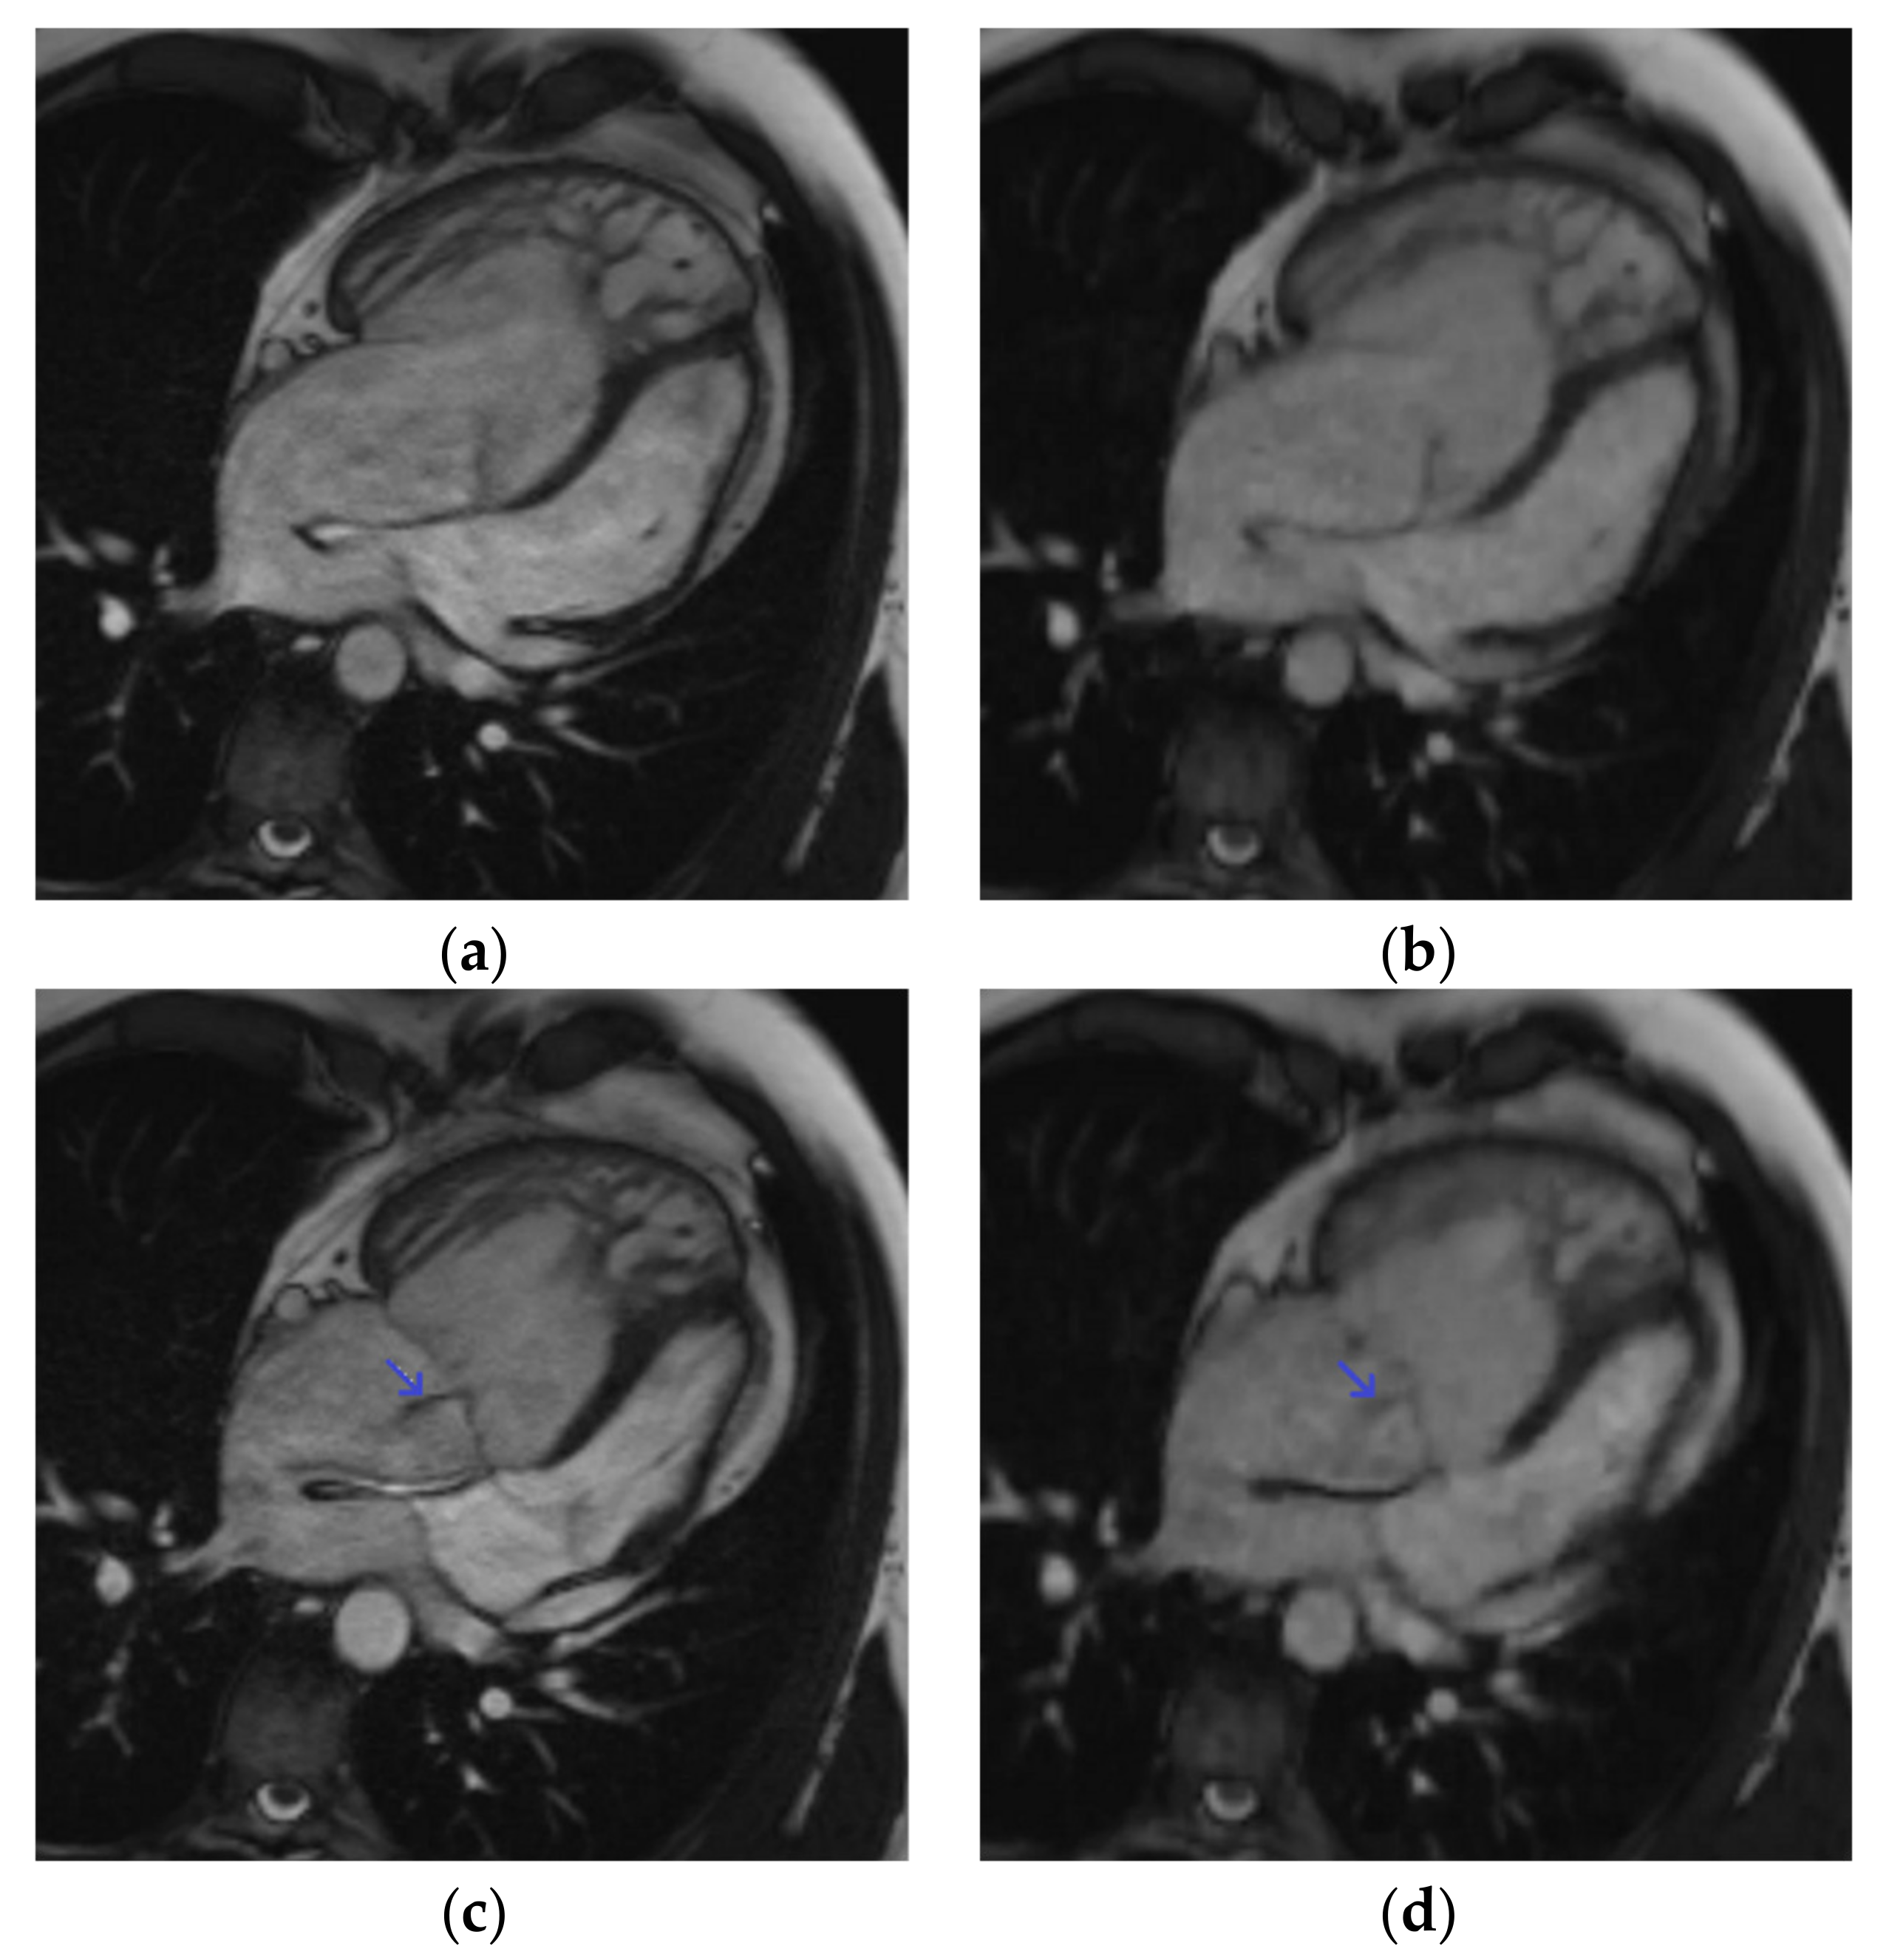

Figure 2.

Four-chamber cine slice acquired with both sequences in a 31-year-old male patient referred for transposition of great arteries after a Senning repair follow-up. SSFPref view in the diastole (a) and systole (c); overall image quality score = 4/4; RVEF = 42%; EDV = 345 mL. The same slices acquired with CSrt in the diastole (b) and systole (d); overall image quality score = 3/4; RVEF = 40%; EDV = 346 mL. The tricuspid regurgitation flow artifact remains conspicuous with both sequences (blue arrow). Abbreviations: SSFPref, reference steady-state free-precession cine; CSrt, real-time compressed-sensing cine; RVEF, right ventricular ejection fraction; EDV, end-diastolic volume.